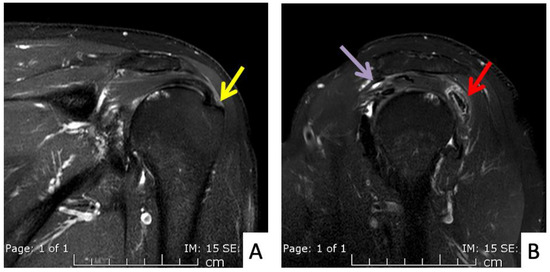

Figure 3.

MRI images of the right shoulder of Patient 1; proton density-weighted images in (A) axial and (B) sagittal views reveal a large amount of fluid in the subdeltoid bursa (yellow arrow). The images also reveal additional subscapularis tendinosis and chondromalacia of the glenohumeral joint, indicating background osteoarthritis.

The fourth case was a 71-year-old Austrian male who began to feel left shoulder pain one day after a second dose of AstraZeneca vaccine. The injection was given with a 1.5-inch 25-gauge needle and the landmark was 1 fingerbreadth below the mid-lateral edge of the acromial process (Figure 2B). The needle direction was perpendicular to the skin. Right shoulder pain was the only symptom, as he had full range of shoulder motion. His pain did not improve after 6 weeks and he finally came to the orthopedic clinic. An MRI of his right shoulder showed a thin layer of subacromial-subcoracoid bursitis and a low-grade partial tear of the supraspinatous tendon (Figure 5A,B). He was given oral prednisolone (30 mg/day) for 10 days and his pain began to improve after 1 day with full return to normal activities in 2 weeks.

Figure 5.

MRI images of the left shoulder of Patient 4; (A) coronal and (B) sagittal T2-weighted images of the left shoulder reveal a small, partial-thickness, bursal surface tear at the footprint of the supraspinatous tendon (yellow arrow). Increased signal intensity of the myotendinous junction of the infraspinatous tendon indicates muscle strain (red arrow). An edematous subacromial bursa with thin fluid (purple arrow) was also observed.